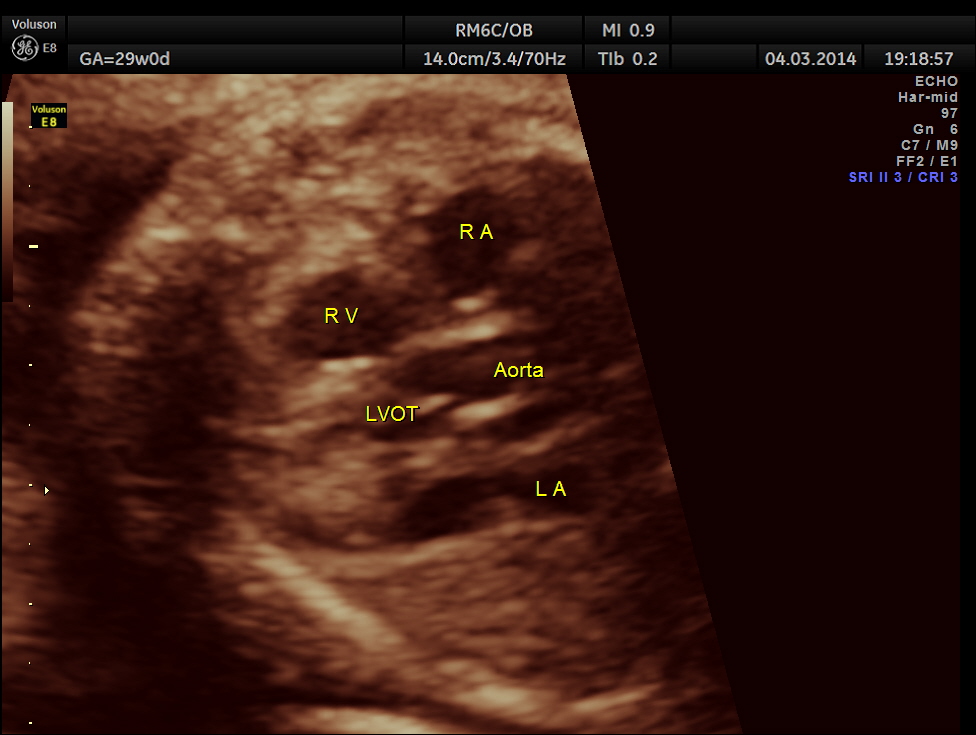

Images of the other organs are given below.